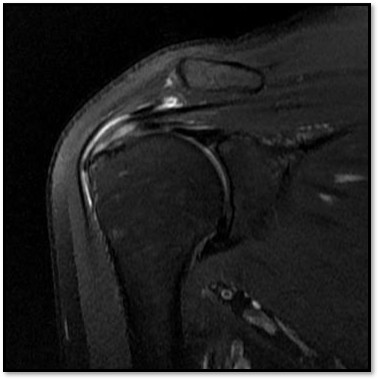

MRI와 초음파를 다시 검토했습니다.

회전근개 극상건의 관절면측(articular-side) 부분파열.

MRI: 극상건 관절면측 부분파열 (약 40%)

MRI: 극상건 관절면측 부분파열 (약 55%)

MRI: 극상건 관절면측 부분파열 (약 30%)